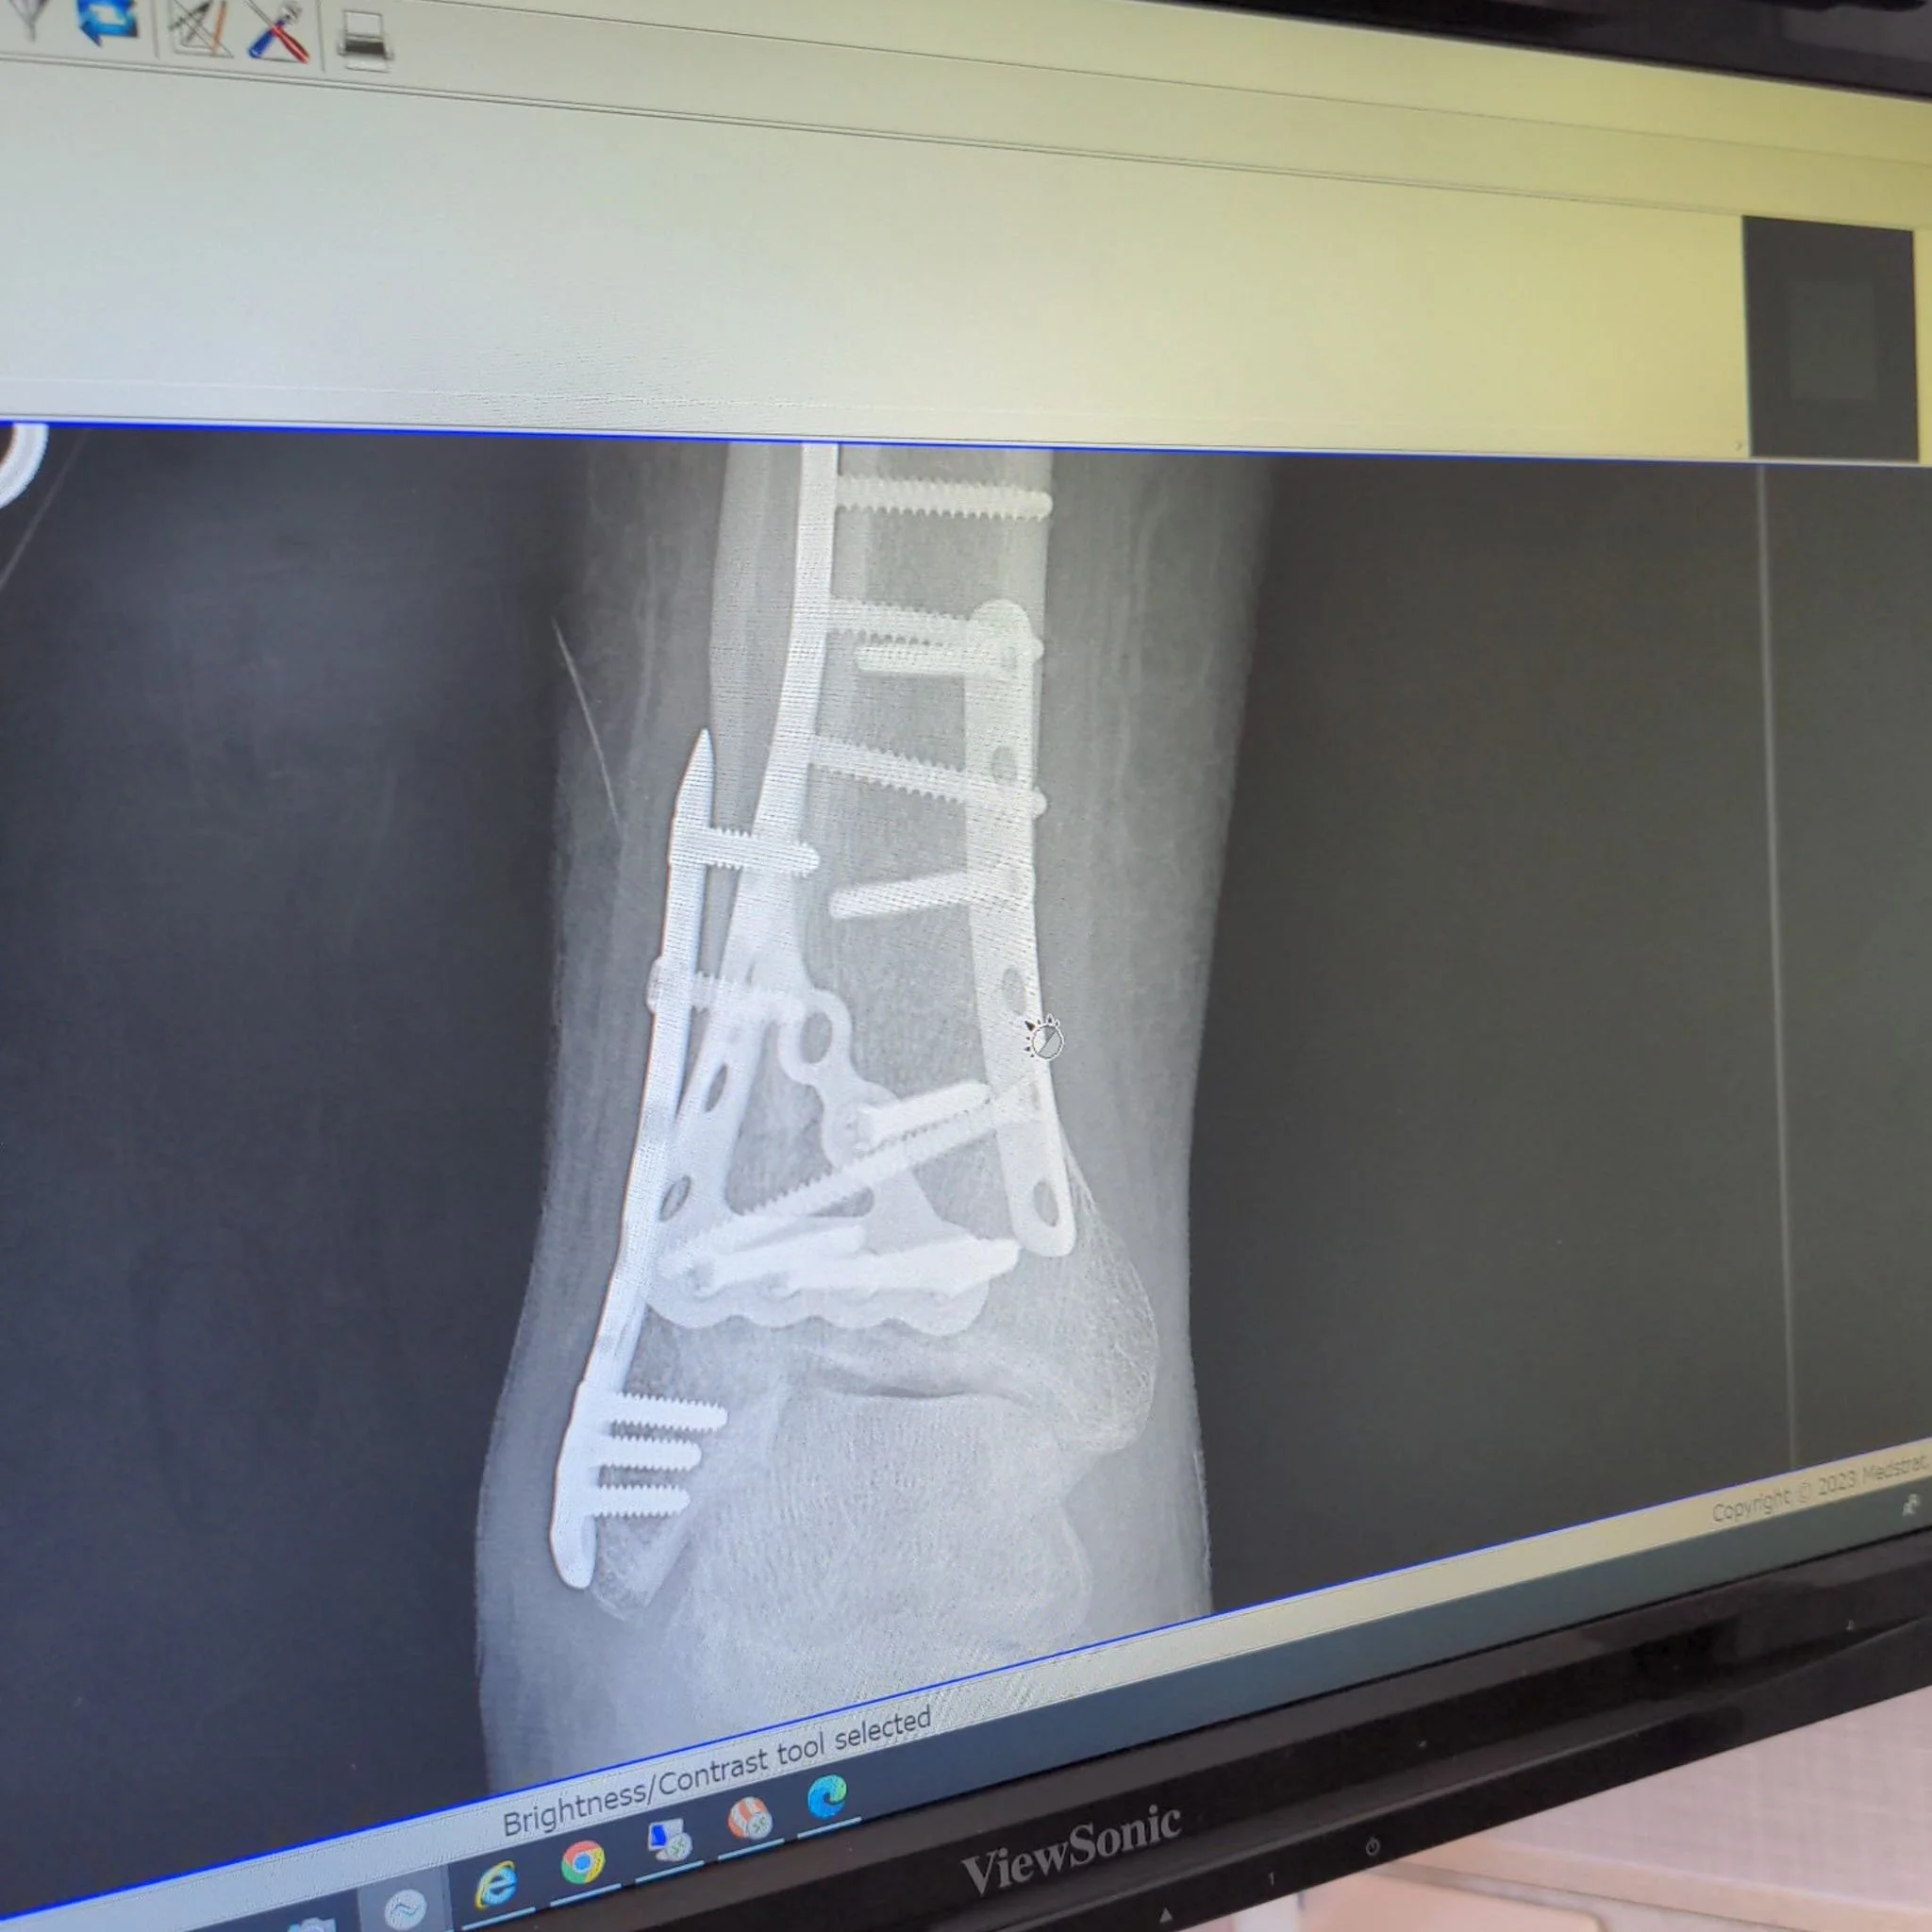

And then, on a steep black I do all the time, not tired, snow was great, I came off the mountain and that was the end of all that. Pretty gnarly injury, broken bones all over the place and two surgeries later, I’m on the couch ‘til May. Such a bummer, but the blessings are numerous: My husband and kids stepping up to take care of me and everything I normally do. Neighbors helping with kid transport so kids can keep going to school and sports. Love and gifts and visits from tons of family and friends. Doctors and PAs and nurses who are helping me heal and making all of this temporary. I can work from the couch. I can be part of my people’s lives from the couch too, it just looks a little different. And, now that I’m off pain meds, more time to write and draw and photograph things and just generally create.